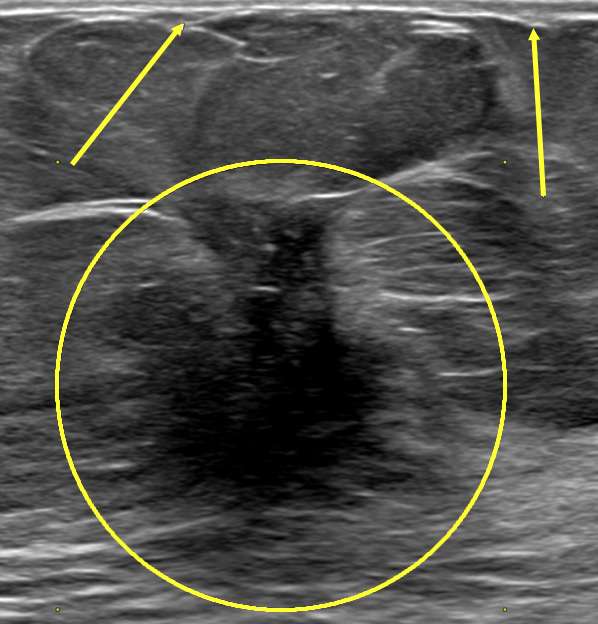

Figure 3: Nipple Retraction on mammogram. Patient presented for right nipple changes. Mammographic MLO and CC projections demonstrate a retracted nipple (arrows) overlying an irregular mass in the subareolar region with associated architectural distortion (circles) in the right breast. Left breast included for comparison.